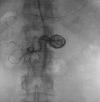

Visceral artery aneurysms are rare, with a 25% rupture risk and an associated 70% mortality. A 55-year-old woman with progressive epigastric pain was found to have multiple large superior mesenteric artery (SMA), branch, and gastroduodenal artery aneurysms along with an occluded celiac artery trunk with hepatic flow dependent on the aneurysm branch. Management included antegrade aortohepatic artery bypass with gastroduodenal artery ligation, followed by SMA stenting and aneurysm coiling. This case is novel, given the diffuse pattern and rarity of SMA and branch aneurysms. This hybrid surgical management highlights innovative strategies to minimize morbidity without compromising definitive treatment of complex visceral artery aneurysms.